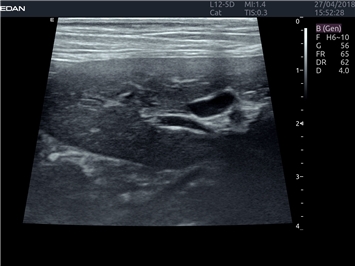

EDAN Acclarix LX4 VET представляет собой профессиональную ультразвуковую систему, специально разработанную для ветеринарных исследований. Сочетание стабильности, высокой производительности и эффективности делает эту систему идеальным выбором для современной ветеринарной практики.

Передовые технологии визуализации:

• Адаптивная визуализация тканей:

• Оптимизация изображения для различных видов животных

• Улучшенная детализация структур

• Универсальные датчики для различных видов животных

• Специализированные предустановки для ветеринарных исследований

• Научно-исследовательских ветеринарных учреждений